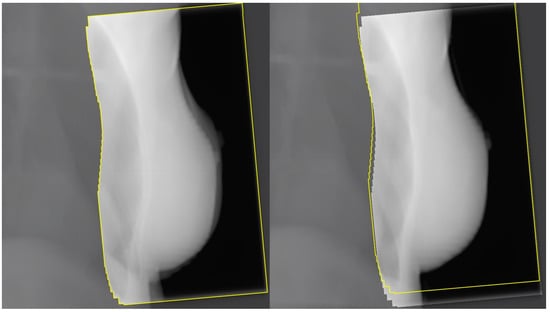

6. Regional Lymph Node Irradiation and Risk of Serious Toxicity